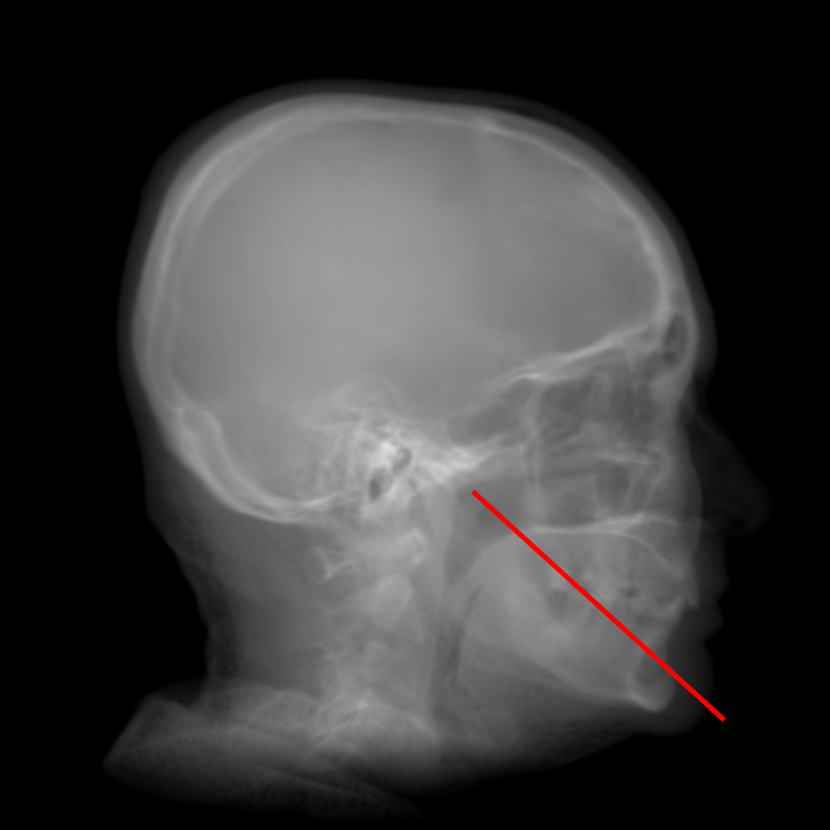

Refer to caption

Fig. 9: Intensity profiles of a chosen line from Figs. 8(a)-(g). The position of the line is marked in Fig. 8(a). The major crests and troughs in the curve of our proposed method are marked by CisubscriptC𝑖\text{C}_{i} and TisubscriptT𝑖\text{T}_{i} where i=1,2,3,4𝑖1234i=1,2,3,4, respectively. Their positions are indicated by the red-dashed and blue-dotted vertical lines respectively. The soft tissue region is marked by S.

For quantification, the intensity profiles of a chosen line from Figs. 8(a)-(g), the position of which is marked in Fig. 8(a), are plotted in Fig. 9. The major crests and troughs in the curve of our proposed method are marked by CisubscriptC𝑖\text{C}_{i} and TisubscriptT𝑖\text{T}_{i} where i=1,2,3,4𝑖1234i=1,2,3,4, respectively. At the position C4subscriptC4\text{C}_{4}, it is clear that the line profiles of orthogonal RayCast and perspective RayCast have low contrast. The profile of MIP100 has high contrast for the crests and troughs. However, the soft tissue part marked by S has too large intensity. The profile of CycleGAN has high contrast as well. Nevertheless, it also introduces undesired crests and troughs, for example, those between T4subscriptT4\text{T}_{4} and C4subscriptC4\text{C}_{4}. In addition, the position of C4subscriptC4\text{C}_{4} is also shifted. Compared with the original orthogonal RayCast, the profile of orthogonal RayCast from the enhanced volume has better contrast at all the positions of C1C4subscriptC1subscriptC4\text{C}_{1}-\text{C}_{4}. With the original sigmoid transform, the contrast is further enhanced. However, at the soft tissue part marked by S, it almost has a constant value. The profile of our proposed modified sigmoid transform overlaps with that of the original sigmoid transform except for the soft tissue part, where the contrast of the soft tissue is brought back.